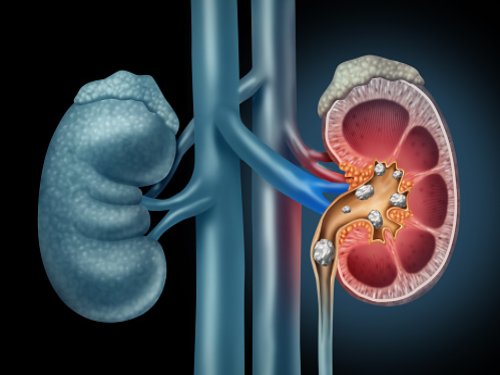

Calcium oxalate stones are the most common type of kidney stone affecting western society. In the United States alone, about one million people develop kidney stones every year, with adults between the ages of 20–40 most commonly affected. To help mitigate the risk of developing calcium oxalate stones, in particular, it is recommended to limit ...click here to read more